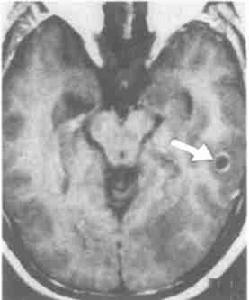

6.腦CT檢查;CT診斷顱內腫瘤主要是根據腫瘤組織的密度改變和腫瘤對腦室系統的壓迫移位來判斷。有些腫瘤顯示密度高,CT圖像清晰;有的腫瘤因有鈣化沉著,對比清楚;有些腫瘤或因瘤組織壞死,或因病灶周圍水腫等變化而顯示為均勻或不均勻之低密度區。顳葉腫瘤多為膠質瘤和腦膜瘤,CT檢查多顯示為高密度區,亦有少數腫瘤有鈣化,囊變、壞死、水腫等顯示其不同的密度變化。側腦室和第三腦室常見受壓、變形、移位等。